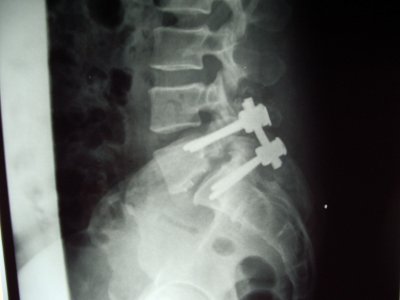

Espondilolistesis